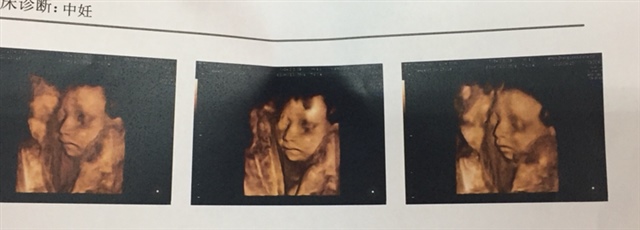

孕22周+2天

鼻子真心漂亮

怀孕用户oqKe[帖主]:谢谢您!好开心